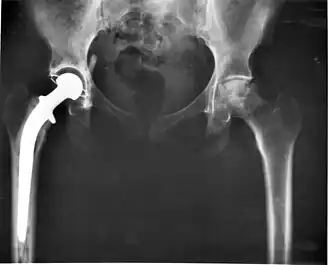

Эндопротезирование суставов

Состояние после эндопротезирования правого тазобедренного сустава. Исход правостороннего коксартроза

При наличии показаний к операции методом выбора может быть эндопротезирование суставов. В настоящее время разработаны и успешно применяются эндопротезы тазобедренного и коленного суставов. При остеопорозе эндопротезирование осуществляется конструкциями с цементным креплением. Дальнейшее консервативное лечение способствует снижению сроков реабилитации оперированных больных и повышению эффективности лечения.